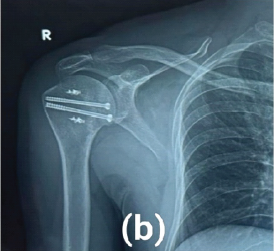

Complex Scapulothoracic Disruption Managed with Scapular Dual Column Plating and Acromion Tension Band Osteosynthesis: A Radiological and Functional Success Story

Avik Kumar Naskar , Himanshu Pradeep Ganwir , Vikas Anandrao Atram , Shubham Shivlal Pawar

………………………………p.135-139